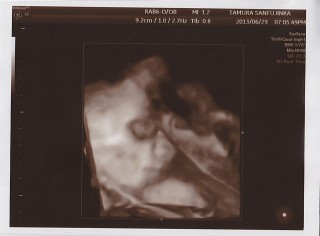

今通ってる産婦人科での健診は今日で最後☆ 次からは里帰り先での診察になります(^^) 今日が4Dラストチャンスでしたが、ママの背中側を向いていた為お顔は見えず(´・ω・`) 可愛いお耳だけが見えましたー! ラストチャンスだったからお顔見たかったな(^^) BPD7.9センチAC24.8センチFL5.5センチ推定体重1546gでした♪ 次は33wの時に里帰り先での健診です! その時には2キロ超えてるかな?! 早く会いたいな♡ 3人目にして初の女の子、みんな楽しみにしてるよ・:*+.\((°ω°))/.:+